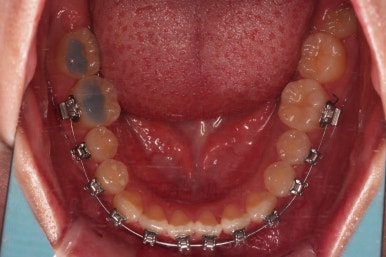

초진 시, 입안의 모습입니다.

아래 중앙선이 윗니의 정중선에 비해 우측으로 많이 쏠려있고요.

전반적으로 아래 치열이 우측으로 가 있어서 특히 송곳니 부분에서의 반대교합이 두드러졌어요.

(아래 송곳니가 위 송곳니보다 밖에 나와있는 상태)

입천장에 장치를 3개월 가량 유지하는 동안 치아에 브라켓을 부착하여 가지런하게 해줍니다.

이번 환자분이 선택하신 장치는 눈에 많이 띄는 윗니는 자가결찰 세라믹(데이몬 클리어, Damon clear), 아랫니는 자가결찰 메탈(엠파워 메탈, Empower metal)을 사용했어요.

장치 부착 후의 모습은 참고해 주시고요.